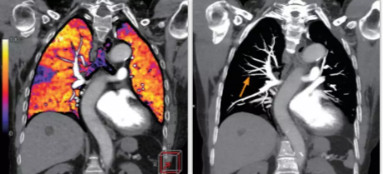

相比傳統(tǒng)成像方式,肺部柔性減影技術(shù)通過(guò)人工智能,對(duì)平掃數(shù)據(jù)和CT肺動(dòng)脈血管掃描數(shù)據(jù)進(jìn)行智能比對(duì),解碼并識(shí)別各個(gè)器官(肺、氣管、肺動(dòng)脈、肺靜脈、主動(dòng)脈等)的空間位置,并在三維空間中進(jìn)行體素級(jí)的柔性配準(zhǔn),從而極大提升了不同序列數(shù)據(jù)的空間位置的一致性。通過(guò)肺部柔性減影技術(shù)可得到肺強(qiáng)化碘圖,可以顯示出傳統(tǒng)CTPA圖像看不到的小栓塞病變,提高了栓塞檢出率,其結(jié)果甚至可與SPECT吻合。

肺智能柔性減影成像功能發(fā)現(xiàn)亞段肺栓塞

此次,佳能對(duì)能譜成像方案也進(jìn)行了升級(jí),結(jié)合了AI的柔性能譜技術(shù)從能譜技術(shù)的四個(gè)基本判別條件——輻射劑量,數(shù)據(jù)精度,覆蓋寬度和能量分離度著手,分別優(yōu)化了以上四種技術(shù),實(shí)現(xiàn)了kV和mA的獨(dú)立切換。高低kV的切換保證了能量分離度;根據(jù)體位自動(dòng)調(diào)整的mA有效降低了輻射劑量;16厘米容積探測(cè)器解決了覆蓋寬度的問(wèn)題;單球管配合AI感知掃描技術(shù)與AI器官柔性配準(zhǔn)算法,確保了數(shù)據(jù)精度。以此作為保障,佳能能譜+灌注的多模態(tài)成像方案僅需一次掃描即可同時(shí)獲得能譜數(shù)據(jù)和灌注數(shù)據(jù)